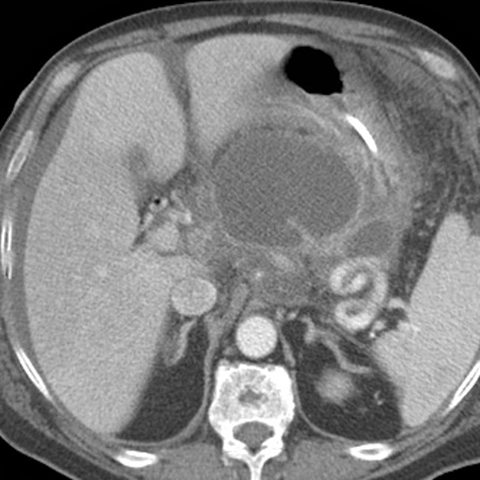

Pancreatic Pseudocyst [1 of 3]